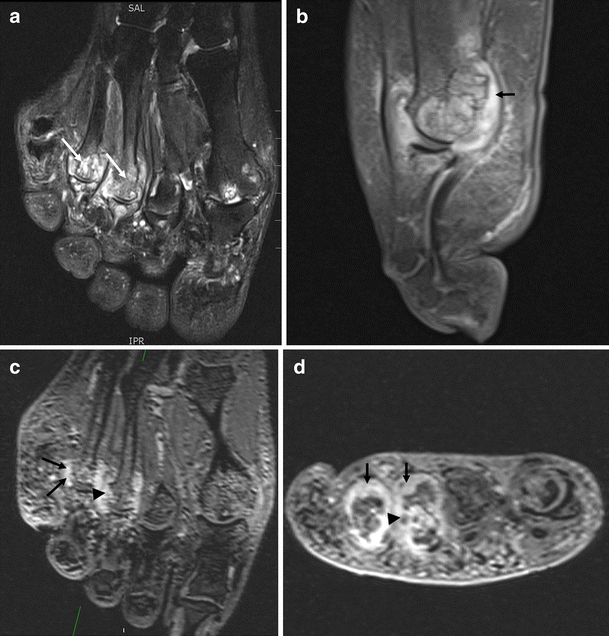

Images through the MTP joints of a patient with RA showing synovitis, bone marrow oedema and bone erosion. a Long axis T2-weighted fat-suppressed image showing extensive bone marrow oedema (white arrows). b Sagittal post contrast T1-weighted image showing synovitis (black arrow). The plantar plate is absent and synovitis extends from the joint to the flexor tendon. c Long axis and d short axis reconstructions from T1-weighted post contrast 3D VIBE images, again showing synovitis (black arrows) and erosion of the metatarsal heads (black arrowheads)